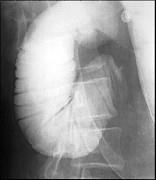

问题 女,14岁,腹胀疼痛,上腹部见胃形,呕吐(胆汁样),影像检查如图,最可能的诊断是 ( )

选项 A.十二指肠综合征 B.机械性小肠梗阻 C.十二指肠憩室 D.十二指肠重复畸形 E.麻痹性肠梗阻

答案 A